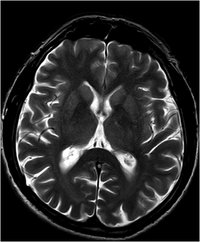

Creutzfeldt-Jakob - T2 - axial

Creutzfeld-Jakob Erkrankung. Typische Signalsteigerung Ncl. Caudatus und Putamen.

(Siehe auch vorheriges Bild)